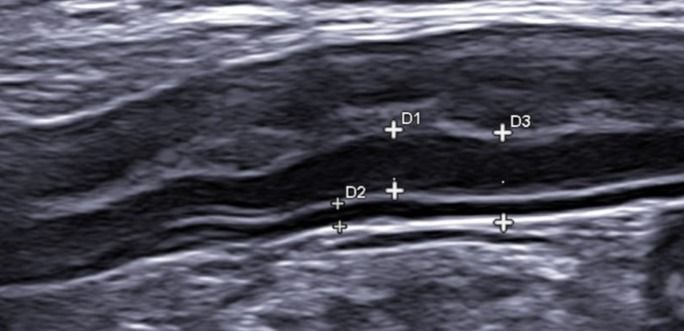

Ultrasound

Our hospital offers cutting-edge imaging technologies that provide detailed internal views of your cat’s organs and tissues, helping us diagnose a wide range of conditions with precision: